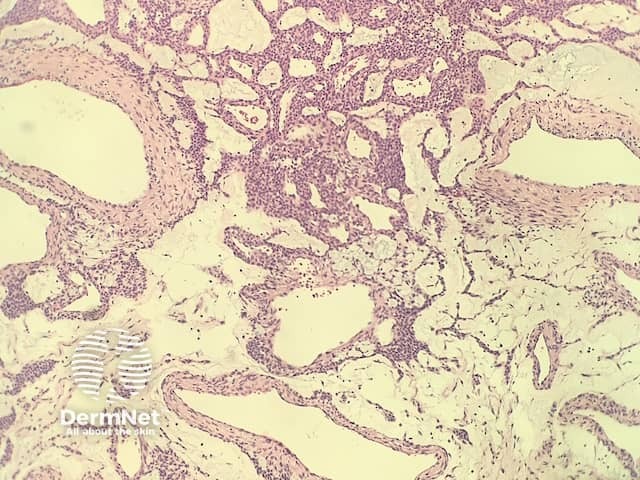

In glomangioma, the histopathology shows dilated venous channels that resemble venous malformations (figures 1, 2). Unlike venous malformations, they demonstrate single to multiple rows of surrounding cuboidal glomus cells (figures 3,4).

Figure 2